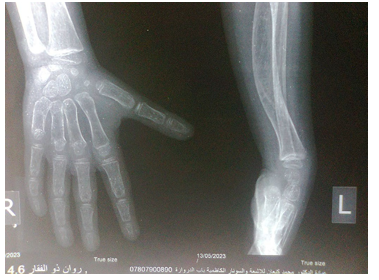

Old radiographs of the younger sister showed osteopenia, fracture in the upper limb, and progressive bowing with no rachitic changes. Figure-3A and 3B show lower limb radiographs showing progressive bowing. Figure-4 (A, B, C, and D) show recent bone radiographs of the younger sister taken during May, 2023 which showed osteopenia, bowing with no rachitic changes. Radiograph of the pelvis showed mild protrusio acetabula (Figure-4A). Radiograph of the wrist showed no rachitic changes (Figure-4B). Radiograph of the lower limbs showed bowing, cortical thinning with scanty spongiosa (Figure- 4C). Lateral skull radiographs showed platybasia (Figure-4D).

Figure-4B: Radiograph of the wrist showing no rachitic changes